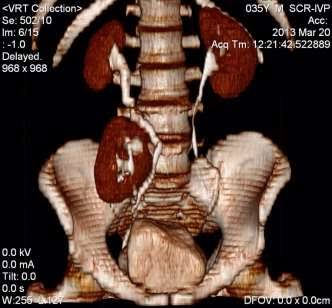

This spinal X-ray appearance is classic for? A. Tuberculosis (Pott's spine) B. Rheumatoid arthritis C. Ankylosing spondylitis D. Osteoporosis #NEETPG #MedTwitter Dr. Akhil 🇮🇳 Antonio Arroyo, MD. Medico Cirujano. Dr. Priyam Bordoloi Dr. Shiv_Kumar Dr. Medica🩺 SAGE MEDICAL⚕️